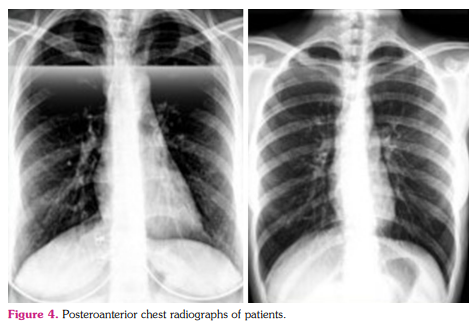

A 45-year-old female (II:5) with rheumatoid arthritis, psoriatic arthropathy, and swelling of the ankles, hands, face, eyes, and abdomen described that she never had 5 min of comfortable time in her life without pain, scratches, and bruises. The patient had difficulty stepping on the ground in the morning for approximately 30 min and mentioned that bruises appear without a reason on her body. Three of her children applied to our department. Two of them (III: 8,9,10) had similar symptoms with their mother. The 20-year-old elder daughter was also suffering from severe symptoms similar to her mother (Figure 2). A 14-year-old boy had a general skin eruption that does not compatible with urticaria. Proband’s elder sister (II:4) lost her life at the age of 59 as a result of acute lung complications. Posteroanterior chest radiographs were taken twice a year for follow-up purposes. Her elder sister (II:2) and brother (II:1) also had some complications. The pedigree of the entire family is shown in Figure 2.

Proband, who had been followed up in the rheumatology department, did not respond to any treatment despite using colchicine, methylprednisolone (4 mg), leflunomide (10 mg), adalimumab, and indomethacin for her conditions. Her daughter used adalimumab, secukinumab, colchicine, and leflunomide, which were also not effective. Posteroanterior chest radiographs of both the proband and her daughter did not show any signs of lung complications (Figure 4). As a result of the V194L mutation detected in the TMEM173 gene, she and her daughter were diagnosed as SAVI, and the treatment strategy was exchanged with 5 mg oral dosage of JAK3 (Janus kinase 3)-inhibitor tofacitinib two times a day. The patients positively responded to the treatment from the initial use. Complaints decreased by about 70% in two weeks and completely disappeared one month after the treatment (Figure 3). Tofacitinib treatment has been continued for more than one year.